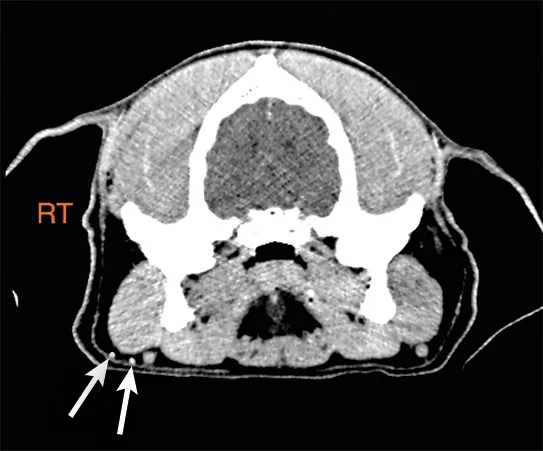

FIGURE 1

CT scan of the head of a dog with an oral tumor after periotumoral injection of iodinated contrast material, which can be seen in the right mandibular lymph node (solid arrows) as compared with the left mandibular lymph node (dashed arrows), indicating the right mandibular lymph node is the SLN.